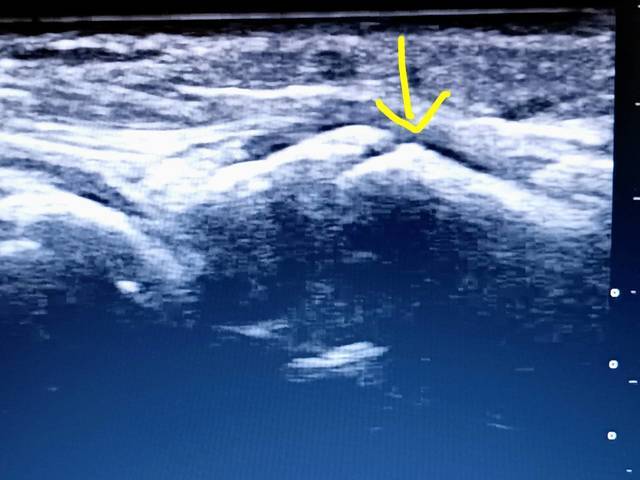

矢印が手首の近くの背中側の骨が少しヒビが入っている不全骨折です。剣道をやっている中学生が、竹刀で打たれて、打撲と思ったら、腫れもあり、骨も折れていたということです。エコーがあればもし、骨が折れても見逃すことがなく、すぐに整形外科に紹介することができます。